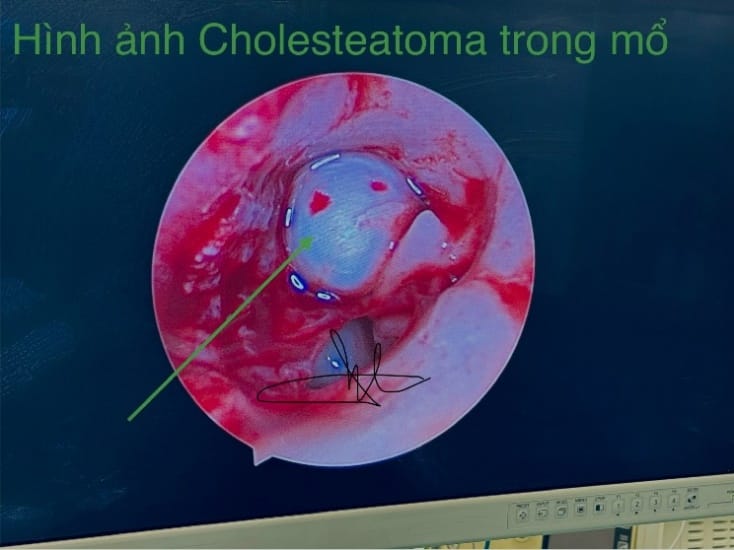

Hình ảnh nội soi tai khối Cholesteatoma.

Khối u nang hình tròn hoặc hình bầu dục, là một u nang được bọc bên ngoài bởi một màng dai có màu trắng ngà như ngọc trai. Ngoài cùng là lớp quanh màng mái gồm có mô hạt có lẫn các tế bào lympho và các bạch câu hạt trung tính.

Lớp màng mái: Mô vảy lát tầng sừng hóa với 4 lớp như 1 cấu trúc biểu bì bình thường (lớp tế bào đáy, lớp Malphighi, lớp hạt và lớp sừng), tế bào Langerhans (là những tế bào lớn hơn tế bào biểu bì bình thường) và những hạt Keratin trong suốt.

Lớp trong cùng: chủ yếu là Lipid, Protein và Cholesterin.